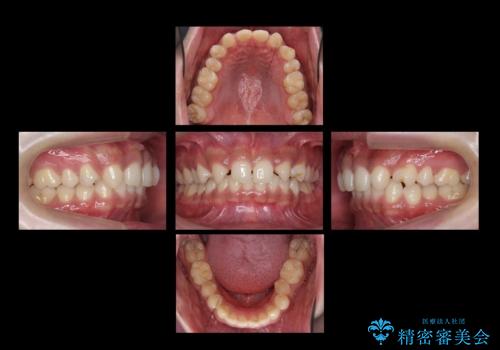

- 前歯の隙間を気にして来院。

生まれつき上の歯が二本少ない状態でした。

バラバラに位置している前歯の位置を矯正治療で修正してからブリッジを装着しています。

また、全体矯正もご希望でしたので下の歯のがたつきや、すれ違っているかみ合わせも治療しています。

矯正治療によって事前に歯の位置を修正しているため、ダミーの歯の大きさも調整し、自然な仕上がりにしました。また、犬歯のねじれを治してから削っているため、神経をとらずに歯の形を整えることができました。

親知らずは矯正前に抜歯しています。